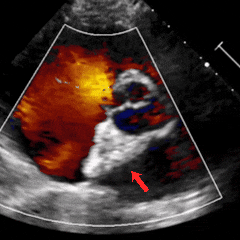

经胸右心声学造影:经左肘静脉注入震荡生理盐水(8mL生理盐水+1mL回抽静脉血+1mL空气经震荡制成),上腔、右房依次显影,造影剂完全充盈右心后,平静呼吸时,左房内即可探及微泡回声,约20-30个/切面/帧;瓦氏呼吸释放即刻,左房内探及微泡回声,不可计数。

术前静息状态经胸右心声学造影(中量)

术前瓦氏动作后经胸右心声学造影(大量)